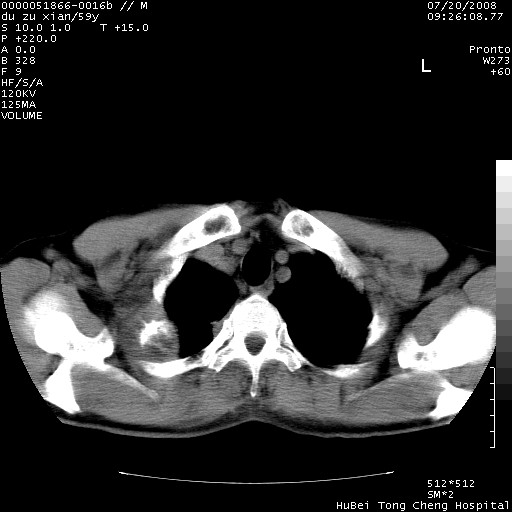

以下是引用宇宙ct在2008-8-25 23:21:00的发言:[br]右肺周围性肺癌并肋骨转移,纵隔淋巴结转移。

以下是引用zsl6918在2008-8-25 22:40:00的发言:[br]右肺周围性肺癌并肋骨转移,纵隔淋巴结转移。

以下是引用zy_zj在2008-8-26 15:24:00的发言:[br]单从病变本身,我倾向良性炎性病变,但肋骨转移了,所以说是考虑右肺周围性肺癌并肋骨、纵隔淋巴结转移可能性大。